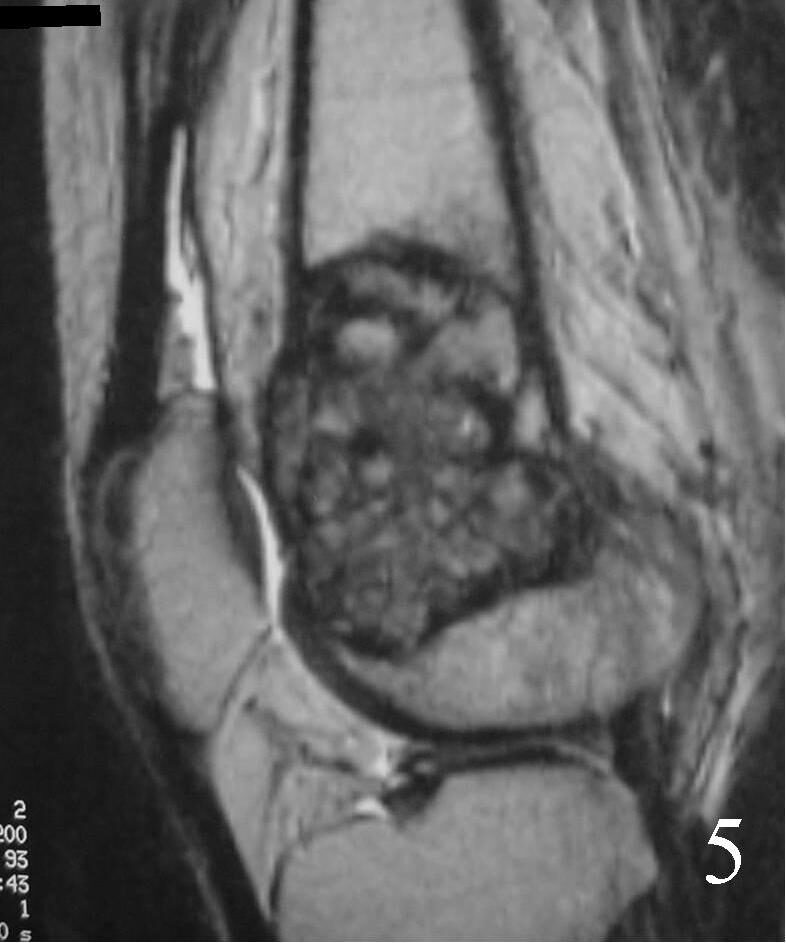

MRI

- They will be low to intermediate on T1-weighted images, and intermediate to high on T2-weighted images (Fig. 4, 5, 6)

Fig. 5 Sagittal T1 MRI shows the soft tissue extension anteriorly.